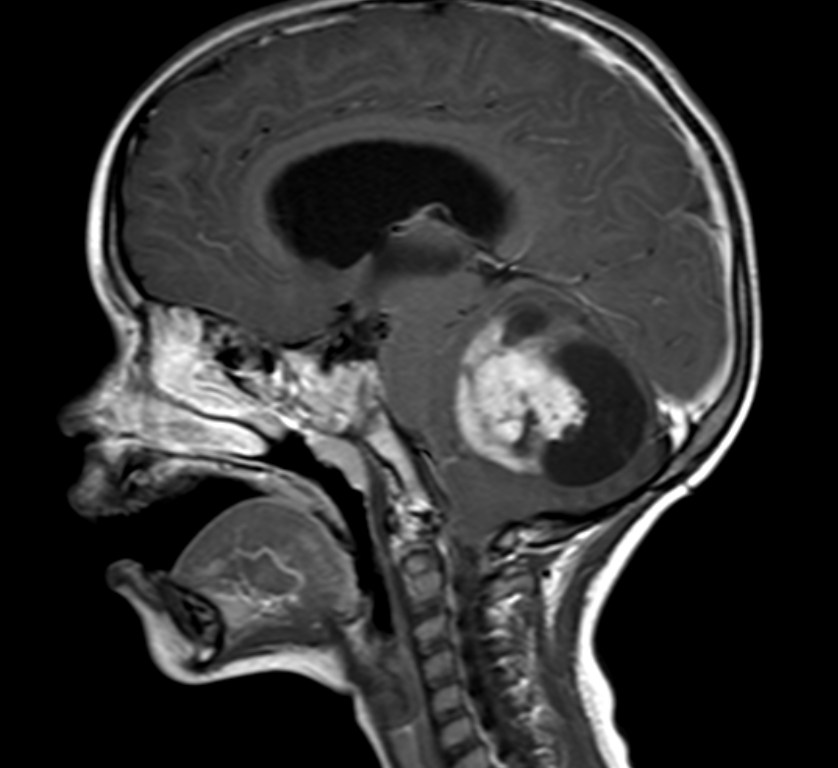

Astrocytomas are the most common type of glioma and contain the most detrimental subtype of brain cancers, glioblastoma multiforme. Astrocytomas affect the astrocytes in the brain, which make up the blood-brain barrier. Xia et al. from Purdue University looked to study the effect of SUMO-specific protease 1 (SENP1) knockout in cell lines derived from astrocytoma patients.

- Image retrieved from: https://pedclerk.bsd.uchicago.edu/page/childhood-astrocytomas